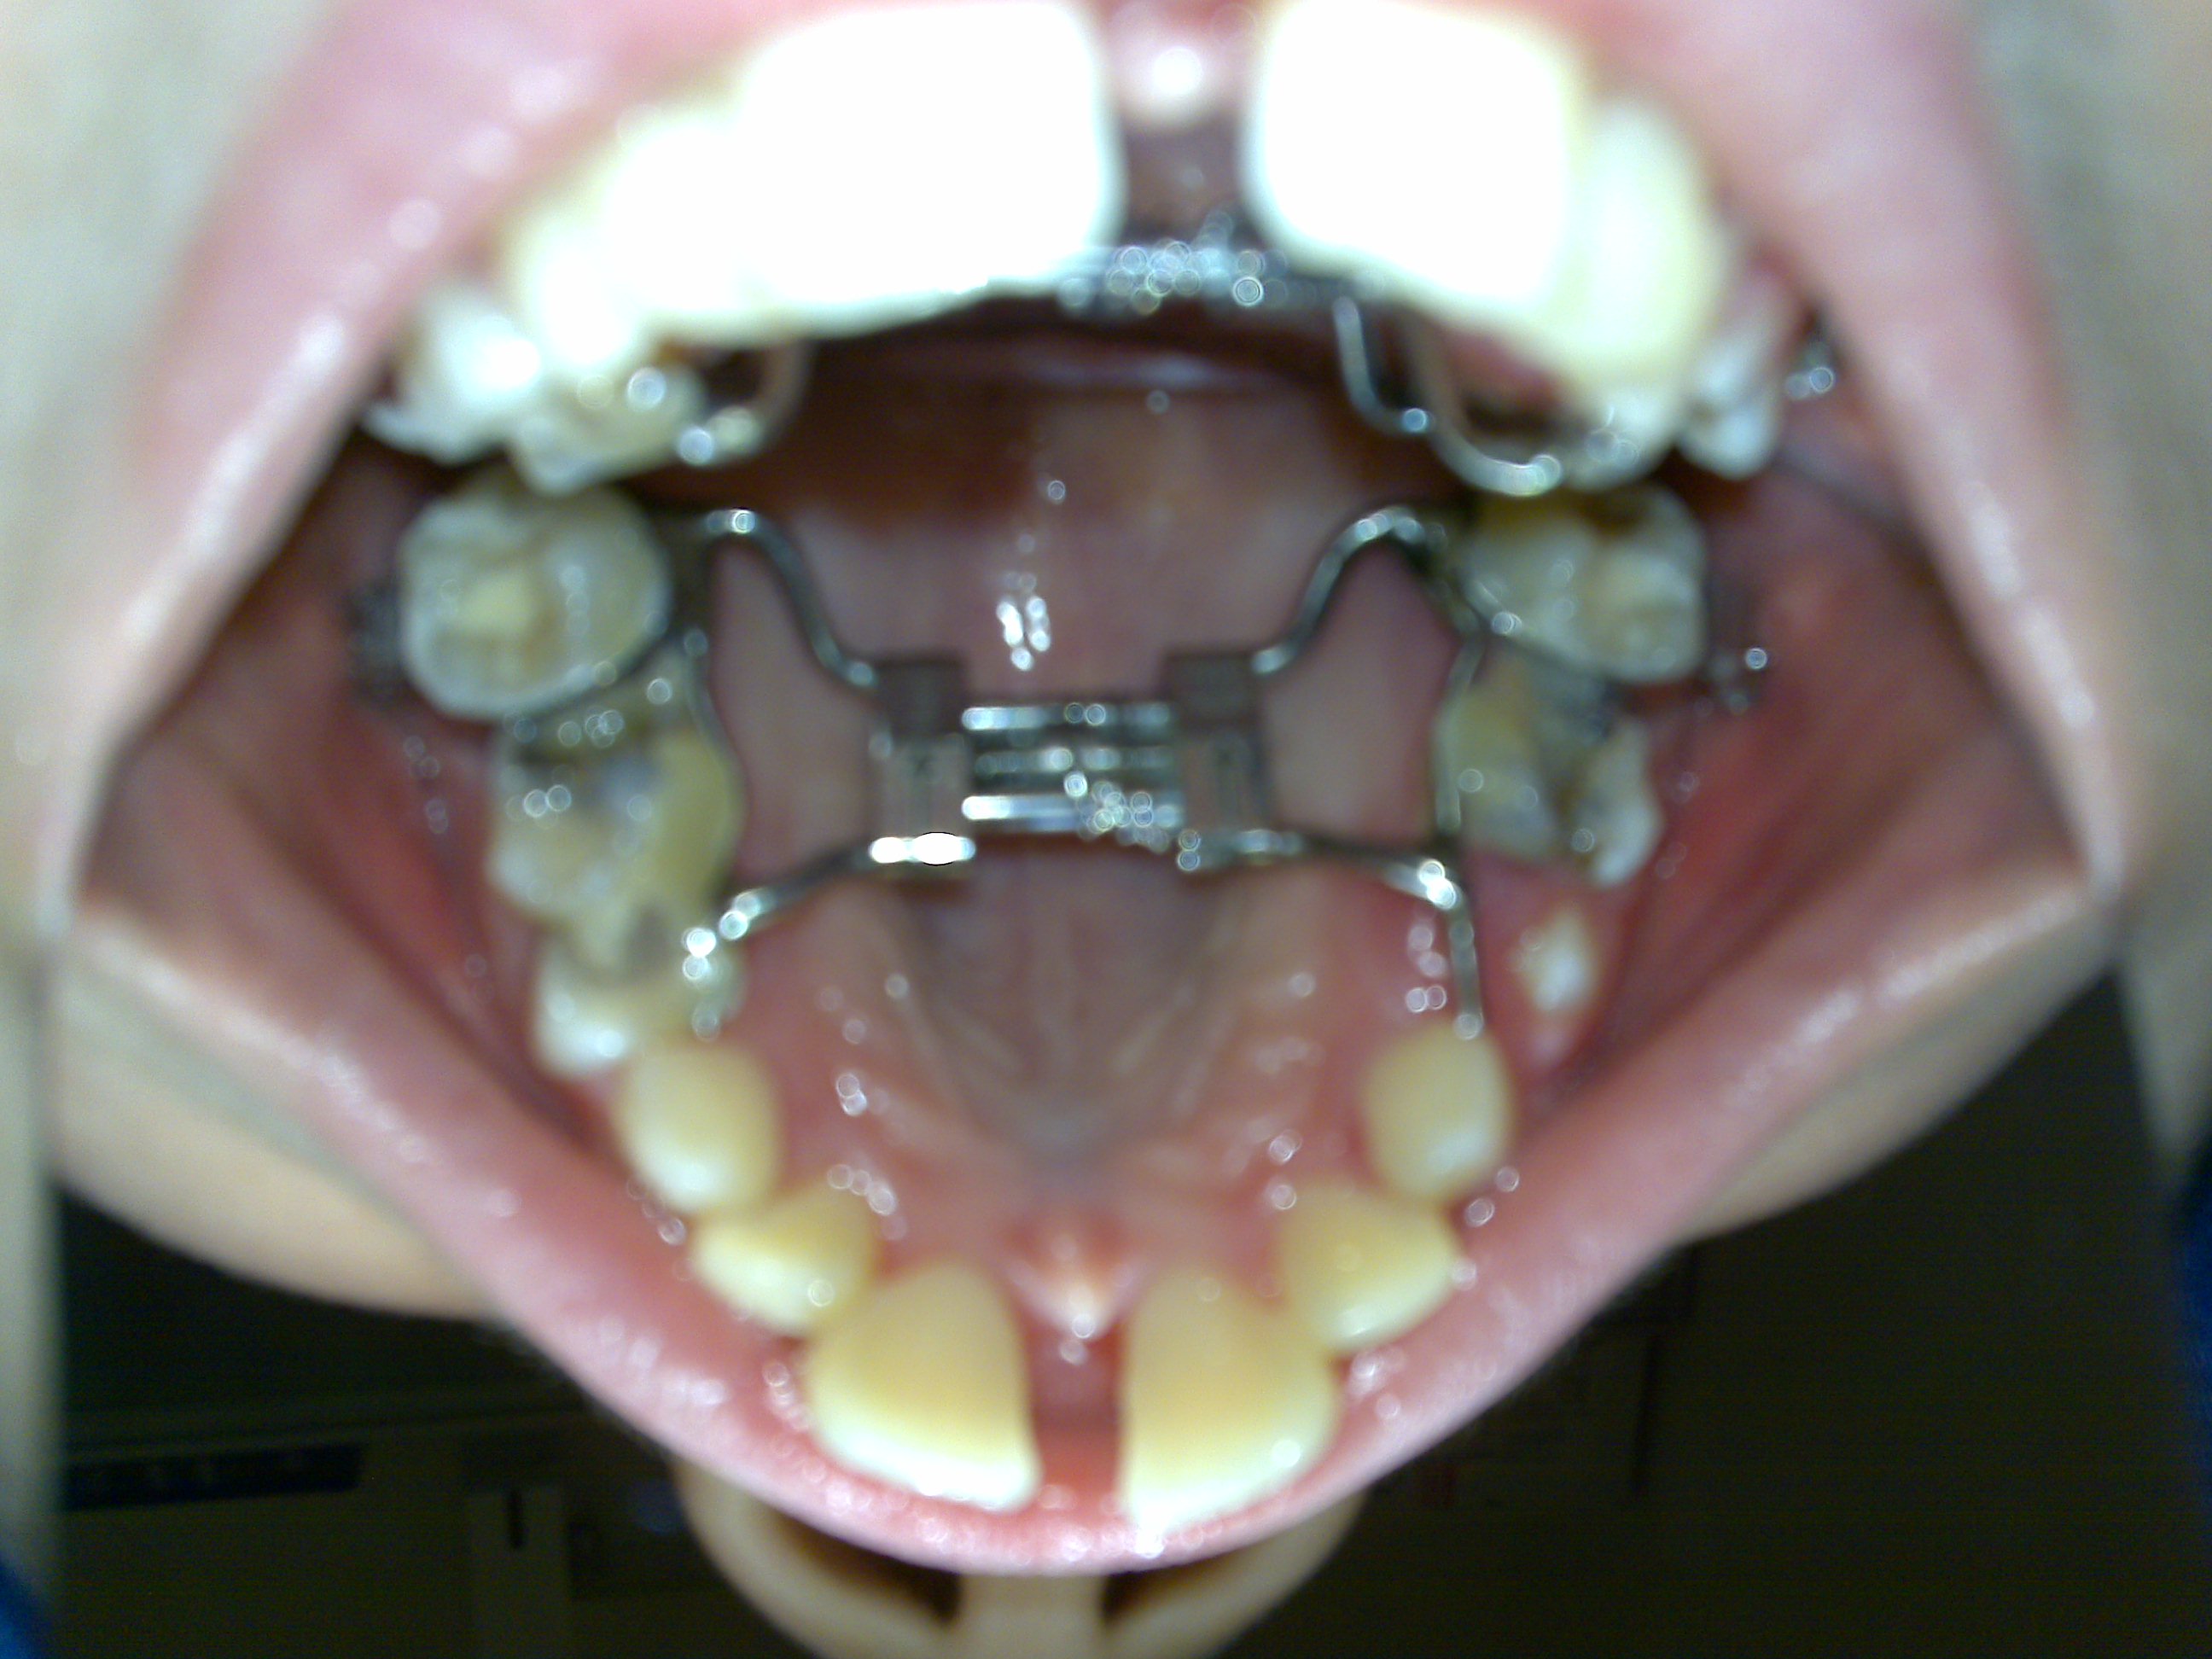

Sono la mamma del bambino di 9 anni e mezzo che ha scritto qualche giorno fa. Ringrazio vivamente per le risposte date e la velocità con la quale avete risposto, non lo immaginavo. Vi invio le radiografie che ho fatto insieme ad una foto degli incisivi e del frenulo. Vi preciso che uno dei medici interpellati e di cui vi ho già scritto, relativamente alla recessione si è espresso dicendo che per fattore genetico al bambino manca l’osso e quindi questa recessione potrebbe averla su tutti gli altri denti, per cui l’unica soluzione plausibile è innesto di osso. Il dente su cui c’è la recessione mi sembra così scollato che temo possa cadere. Inoltre vorrei chiedere conferma relativamente ad alcuni dubbi: 1) Che differenza c’è tra l’uso dell’apparecchio palatale fisso e quello mobile e quale dei due è più valido.? 2) Cosa indirizza un dentista verso l’uso di un tipo o dell’altro e la tempistica di utilizzo riferitami è corretta, un anno circa per quello fisso e 2 anni per quello mobile ( i dentisti che l’anno proposto sono diversi)? 3) L’osso dentale si rigenera spontaneamente al di sotto della gengiva, qualora dovessero fare al bambino una ricostruzione gengivale con una porzione di tessuto molle palatale, o comunque senza ricostruzione e procedendo con gli interventi di pulizia della placca, ortopedia e raddrizzamento dei denti che mi sono stati proposti? 4) Secondo voi il parodontologo va consultato subito o successivamente, in quanto non in tutti gli studi dentistici che ho visitato mi sembra che si avvalgono di tale figura.? I dubbi sono molti e sono insorti in quanto ho deciso, forse erroneamente, dopo i primi pareri alquanto discordi sul da farsi di rivolgermi a più studi dentistici. Vi ringrazio ancora per la disponibilità e per eventuali altre risposte che vorrete darmi.